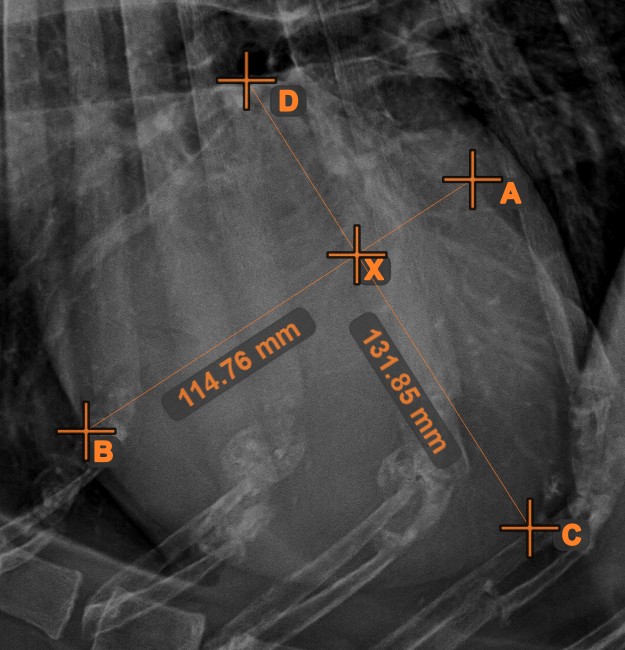

Linienkreuzung¶

Lokalisieren und markieren Sie schnell und präzise den Schnittpunkt zwischen zwei vorhandenen Linien mit dem Werkzeug Linienkreuzung.

Wählen Sie das Werkzeug aus der linken Symbolleiste aus und weisen Sie es einer der verfügbaren Maustasten zu. Wählen Sie zwei bereits in der Szene gezeichnete Linien aus, um die Messung abzuschließen. Der Schnittpunkt der Linien wird automatisch berechnet und in der Szene markiert. Der Schnittpunkt zweier Linien wird stets mit dem Buchstaben X markiert.

Informationen

Wenn sich zwei Linien nicht direkt schneiden, wird der Schnittpunkt ihrer verlängerten Projektionen in der Szene markiert.